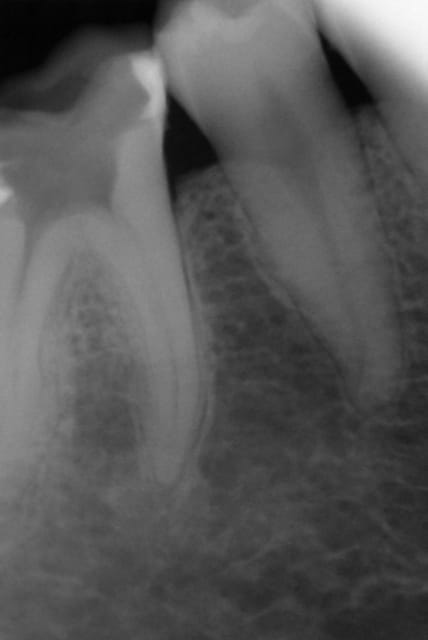

vous en pensez quoi de cette endo?

j'ai fais cette endo mardi dernier,la dent etait assez difficile (canaux fins++,4 canaux)

la patiente ressentait une douleur dans le canal disto vestibulaire,(malgré troncu+intra-septale)

je n'ai pas réussi à aller plus loin d'ailleurs sur ce canal.

je ne suis pas super satisfaite au niveau radio sachant que je doit couronner.

en plus c'etait avec le reciproc que j'utilisait pour la 1ère fois.

j'y ai passée beaucoup trop de temps déjà(plus d'une heure)

que feriez vous?

couronne d'emblée ou reprise de certain canaux la prochaine fois?